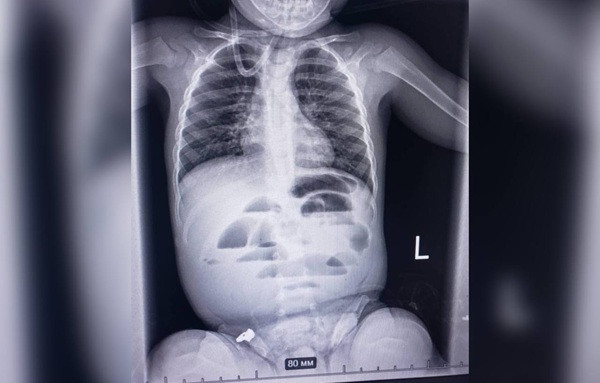

Малюка доставили до лікарні з підозрою на кишкову непрохідність. Проведене рентгенологічне обстеження показало характерні ознаки цього стану. Команда лікарів різних спеціальностей ухвалила рішення про термінову операцію.

Під час операції виявили стороннє тіло, що повністю перекривало просвіт кишечника. Ним виявилася гідрогелева кулька діаметром до 3 см.